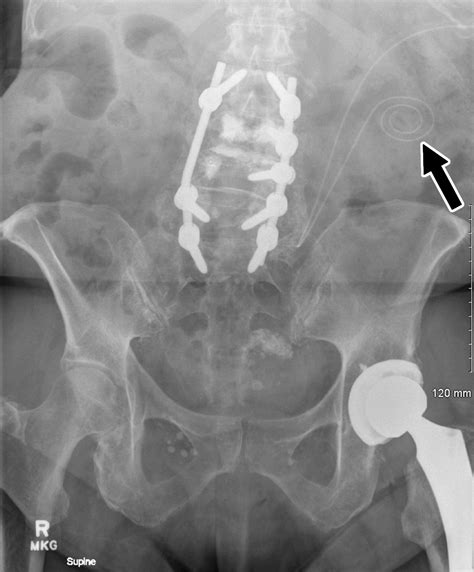

There are several methods used for Pd Catheter Placement, each chosen based on the patient's anatomy, previous abdominal surgeries, and the surgeon's preference. Common techniques include open surgical placement, laparoscopic-assisted placement, or percutaneous methods performed under fluoroscopic guidance. Regardless of the surgical approach, preparation is a fundamental component of a successful outcome.

Patients typically undergo a comprehensive physical assessment, which may include imaging studies to map out the abdominal wall and pelvic region. Surgeons often identify the ideal "exit site"—the area where the catheter emerges from the skin—to ensure it does not interfere with clothing, belts, or skin folds, which are prone to irritation and bacterial buildup.

On the day of the Pd Catheter Placement, the procedure is performed in a sterile operating room environment. After anesthesia is administered—which may be local, regional, or general depending on the surgical approach—the surgeon creates a small incision. The catheter is carefully threaded into the peritoneal cavity, typically targeting the Pouch of Douglas, which is the lowest point in the abdominal cavity to ensure gravity-assisted drainage.

Once positioned, the catheter is anchored with internal cuffs. These cuffs are critical because they encourage tissue ingrowth, which effectively seals the tract and prevents bacteria from traveling along the outside of the tube into the peritoneal space. The tube is then tunneled subcutaneously before emerging at the exit site. This subcutaneous tunnel acts as an additional barrier against infection.